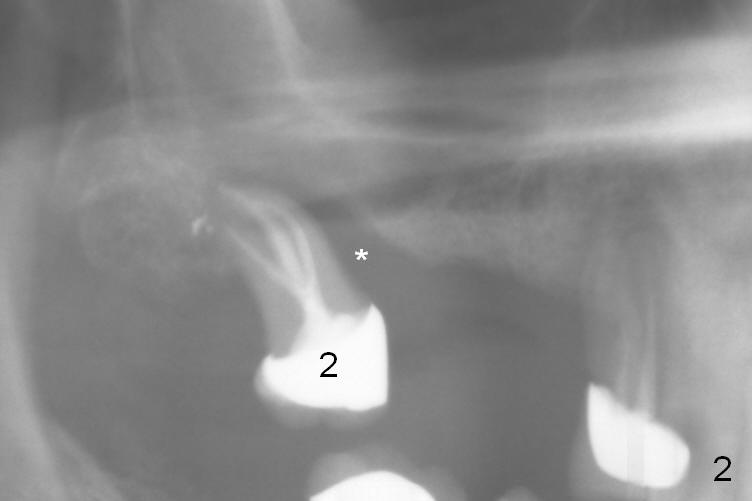

A 71-year-old man had poor dentition 4 years ago (Fig.1). Since then severe bone loss has occurred at the teeth #2 (Fig.2 *), 30 and 31 (Fig.3 *). An original plan is to place implants at #29 and 31 and fabricate a 3-unit bridge. Since the bone height at #31 is limited, primary stability may be questionable. It is advantageous to place 3 implants at #29-31. As the bone loss is severe and the sockets at #30 and 31 are long (Clindamycin), a fairly long portion of the implants at #30 and 31 will be not covered by the native bone (Fig.4 yellow line: 6-7 mm, bare) in spite of using 6 mm cuff (pink) of 7 mm abutments (brown). Use initial drill from DIO Sinus Master Kit with 5 mm stopper at #31 (green line), followed by insertion of a marked parallel pin. Use regular drills with stoppers of 10 and 8 mm at #29 and 30 (green line). Continue osteotomy at #31 with round drills (2.8 and 3.6 mm) with shorter stopper to avoid injury to the underlying Inferior Alveolar Canal (red dashed line). Pack allograft well around the implants at #30 and 31 before placing abutments to reduce periimplantitis and insert collagen plug around the abutments to prevent loss of the bone graft underneath. The last method to secure the bone graft is a retentive, splinted provisional.